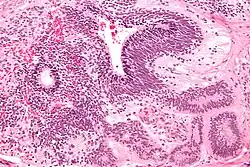

Teratomas

Teratoma are most common germ cell tumor of ovary. Teratomas can be divided into two types: mature teratoma (benign) and immature teratoma (malignant). Immature teratomas contain immature or embryonic tissue which significantly differentiates them from mature teratomas as they carry dermoid cysts.[5] It is commonly observed in 15 to 19-year-old women and rarely in women after menopause.[6] Immature teratomas are characterized with a diameter of 14–25 cm, encapsulated mass, cystic areas, and occasional appearance of hemorrhagic areas.[7] The stage of immature teratomas is determined depending on the amount of immature neuroepithelium tissue detected.[5]